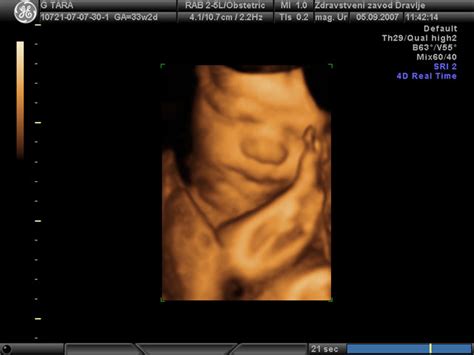

Medenično vstavo običajno diagnosticiramo z ultrazvočnim pregledom (UZ). Ginekolog lahko že med rutinskimi pregledi zazna položaj ploda. V primeru medenične vstave se lahko opravijo dodatni UZ pregledi, da se oceni rast ploda, količina plodovnice, položaj posteljice in preveri morebitna ovitost popkovnice okoli vratu.

V primeru medenične vstave je ključnega pomena skrbno spremljanje rasti in razvoja ploda. Ultrazvočni pregledi omogočajo oceno plodove teže, dolžine okončin, obsega glave in trebuščka. Iz teh meritev se lahko izpeljejo sklepi o morebitnem zastoju v rasti ploda.